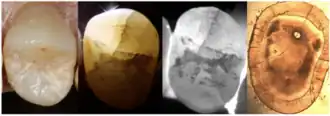

3. Dye Test

Dye application, using agents such as methylene blue can enhance the visibility of cracks (Yu et al., 2022). The dye test is limited in that it can only locate cracks but not assess their progression. Additionally, bacterial infiltration of cracks can cause discoloration that is difficult to remove, affecting aesthetics and treatment outcomes.

4. Transillumination

Transillumination involves using fiber-optic light to illuminate the tooth surface, with light diffraction at the crack helping to locate it (Chanchala HP et al., 2022).

Microscopic Detection

5. Microscope detection

Cracks with width less than 18 μm are difficult to detect with the naked eye, making dental microscopes an essential tool for crack identification.